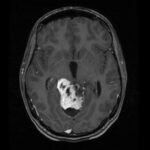

Proton Minibeam Radiation Therapy Shows Promise for Treating Glioblastoma

Radiation therapy (RT) is one of the most common and effective cancer treatments, used in over half of cancer patients. But for some tough cancers, like glioblastoma multiforme (GBM), RT has its limitations. This is because these tumors often have areas with low oxygen (hypoxia), suppress the immune system, resist radiation, and are close to…